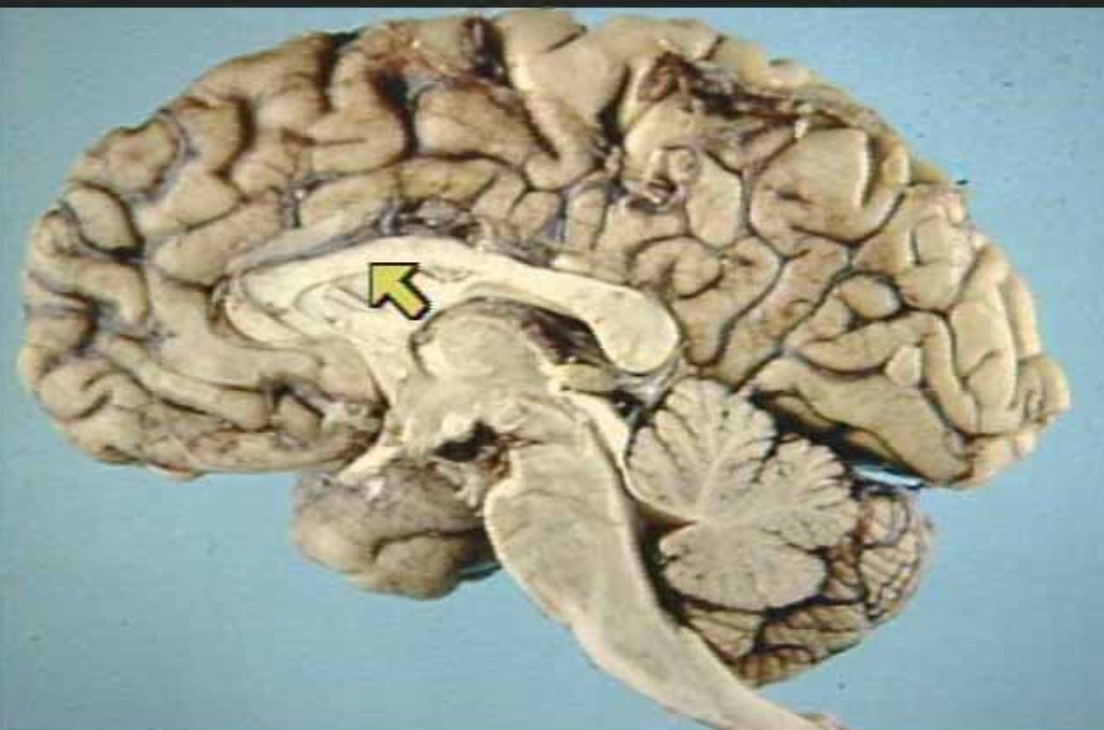

What is the arrow pointing at?

Corpus Callosum (Real Medial View of Brain)